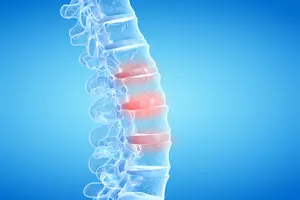

4. 추간판 탈출증 (디스크)

추간판 탈출증, 즉 디스크는 척추뼈 사이의 디스크가 튀어나와 신경을 압박하여 허리 통증을 유발하는 질환입니다. 무리한 운동, 잘못된 자세, 장시간 앉아 있는 등의 생활 습관이 원인이 될 수 있습니다. 허리 통증 외에도 다리 저림, 감각 이상 등의 증상이 나타날 수 있으며, 허리를 숙이거나 뒤로 젖힐 때 통증이 심해집니다. 치료는 약물 치료, 물리치료, 주사 치료 등 보존적인 방법부터 미세 현미경 수술, 내시경 수술까지 다양하며, 환자의 상태에 따라 적절한 치료 방법을 선택해야 합니다. 평소 바른 자세를 유지하고, 규칙적인 운동을 통해 허리 건강을 관리하는 것이 중요합니다.

5. 척추관 협착증

척추관 협착증은 척추관이 좁아져 신경이 눌리면서 발생하는 질환으로, 허리 통증과 함께 다리 저림, 보행 시 통증이 심해지는 것이 특징입니다. 장시간 서 있거나 걸을 때 증상이 악화되는 경우가 많습니다. 척추관 협착증은 노화, 퇴행성 변화 등 다양한 원인에 의해 발생하며, 조기 진단과 치료가 중요합니다.